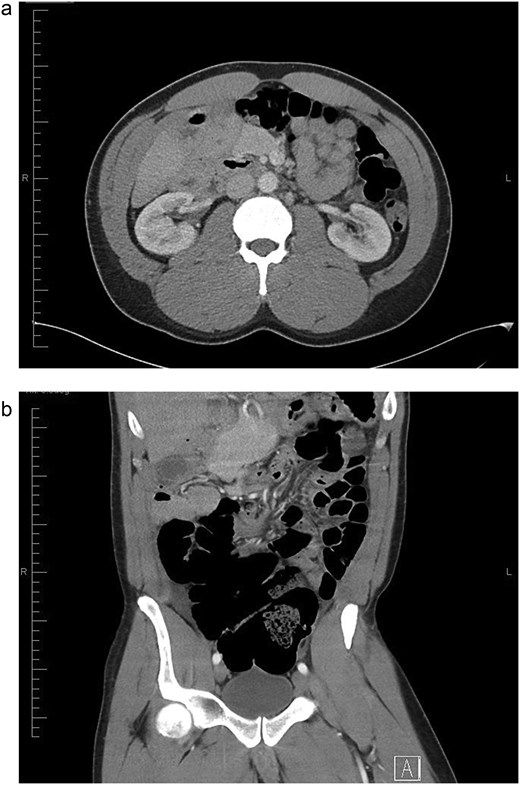

The gold standard for diagnosing malrotation is an upper gastrointestinal (GI) series or a CT scan with oral and intravenous (IV) contrast. In adults, CT is preferred. Characteristic imaging findings include the ‘whirlpool’ sign (Fig. 3a and b), the superior mesenteric vein (SMV) rotation sign, where the SMV lies anterior to the superior mesenteric artery (SMA), as well as right-sided positioning of the bowel, duodenojejunal flexure, and cecum [8] (Fig. 4).

(a) Axial view of CT abdomen with contrast showing swirl sign i.e. swirling of bowel and mesentery; suggesting intestinal volvulus (superior to SMA and SMV. (b) Coronal view of CT abdomen with contrast showing swirl sign i.e. swirling of bowel and mesentery; suggesting intestinal volvulus.